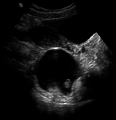

Dermoid cyst in vaginal ultrasonography

A complex cyst due to a dermoid as seen on ultrasound